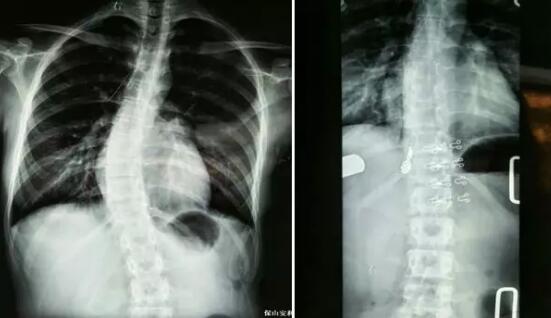

典型案例